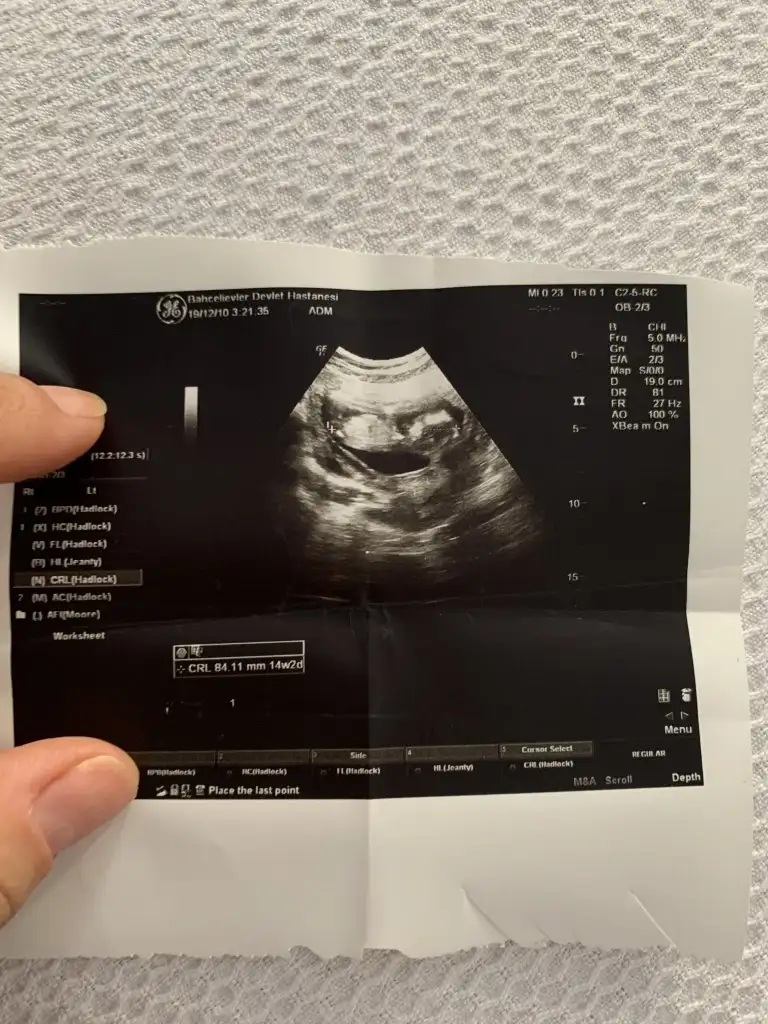

Canım 14+2 dedi doktor cinsiyeti söyledi

Eklentiler

• 99BD7B00-CE13-4C13-9A3C-C16E26C6815A.webp

99BD7B00-CE13-4C13-9A3C-C16E26C6815A.webp

57,2 KB · Görüntüleme: 88